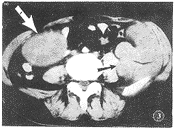

图1 良性神经鞘瘤 CT强化见肿瘤(大箭头)

边缘不规则强化,内部囊变呈低密度区无强化